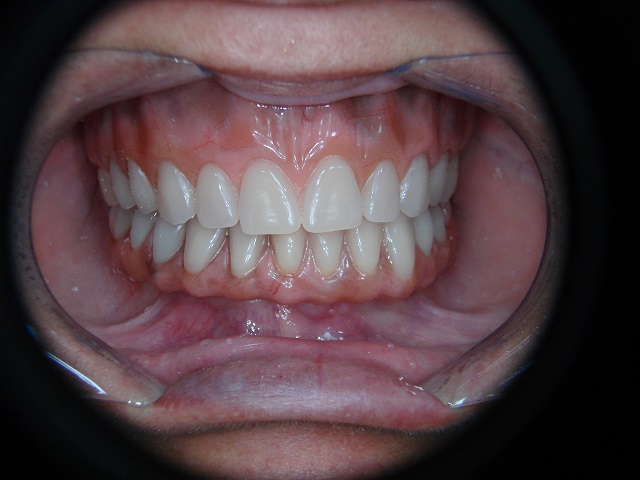

Caso Finalizado